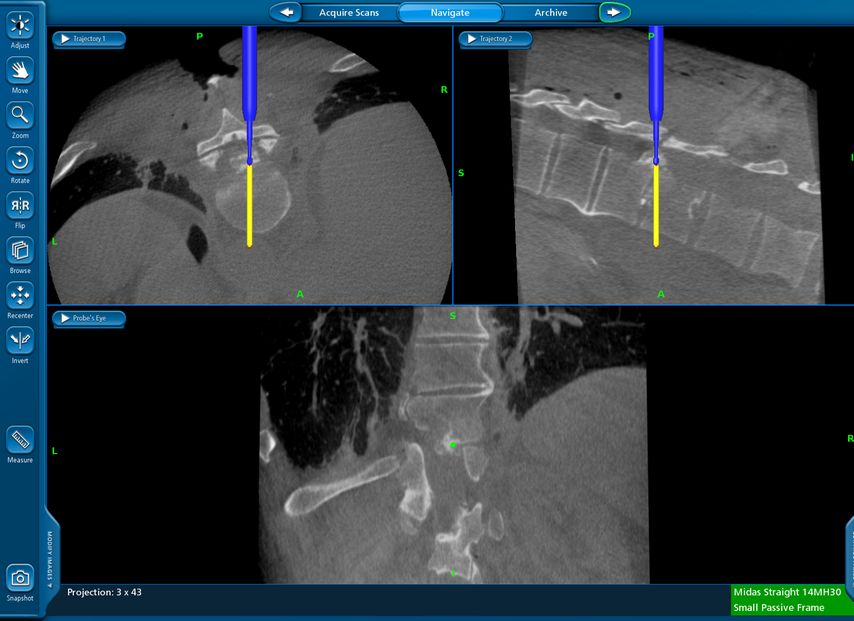

Beispiel für die Implantation zervikaler Pedikelschrauben. In diesem Fall kam es bei einem 61-jährigen Patienten 10 Jahre nach anteriorer zervikaler Diskektomie und Fusion (ACDF) C4/5 und ventraler Verplattung C4–6 zu einer Ankylosierung auch von C6/7. Nach Sturz kam es zu einer Fraktur bei C6/7 mit begleitender Bogenfraktur und auch Beteiligung der dorsalen Ligamenta (Abb. 1 und 2). Klinisch bestanden ausgeprägte Nackenschmerzen und kein neurologisches Defizit. Es wurde die Indikation der dorsalen Verschraubung von C4 auf Th1 gestellt. Intraoperativ wurde routinemäßig zusätzlich eine kleine Referenzschraube in einer Lamina – entfernt von der Dornfortsatz-Referenzklemme für die Navigation – gesetzt. Mit dieser konnte intraoperativ die Genauigkeit der Navigation exakt überprüft werden (Abb. 4 und 5). Mittels navigierter High-Speed-Fräse wurden die Schraubenkanäle vorgebohrt (Abb. 6), im Anschluss wurde der Bohrkanal ausgetastet und die Schrauben wurden implantiert. Abbildung 7 zeigt eine Röntgenkontrolle 3 Monate postoperativ.

Abb. 4: Screenshot der Navigationssoftware intraoperativ (Stealth Station S7). Es erfolgt die intraoperative Verifizierung der Navigationsgenauigkeit mittels kleiner Schraube in der Lamina, positioniert idealerweise entfernt von der Dornfortsatz-Referenzklemme. Die navigierte Fräse wird im Situs exakt auf die Schraubenmitte gerichtet, und die Navigation bestätigt die Genauigkeit | |